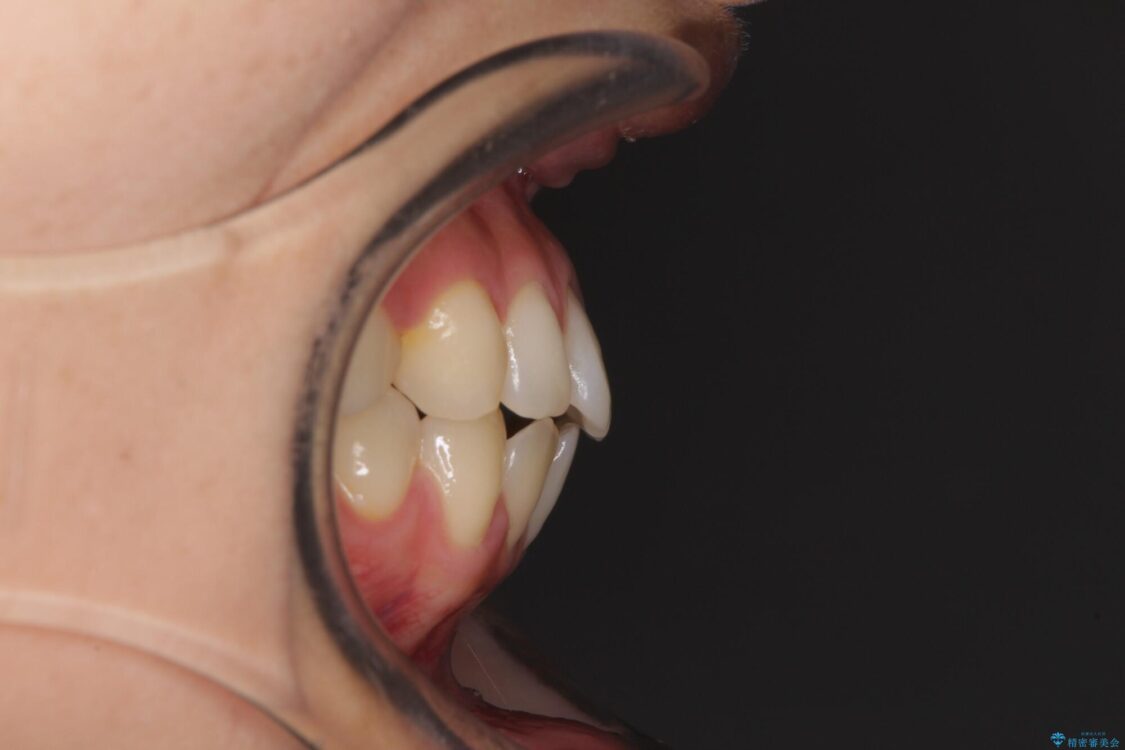

前歯の上下スペースと前歯の隙間を気にして来院された患者様です。

飲み込みや話をするときに舌を突出させる癖が強くあり、それが原因でスペースが空いていました。

治療前

• 隙間だらけの歯列 インビザラインで改善 治療前画像